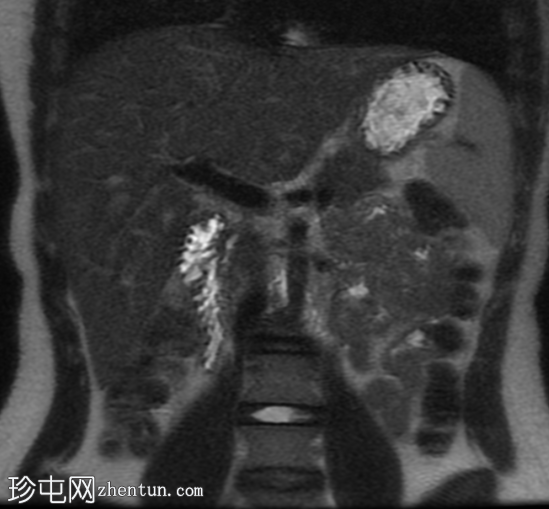

冠状位

T2加权像

子宫前倾位,分区解剖结构正常。矢状位序列可见子宫前壁肌层局灶性边界不清的低信号病灶,但在后续序列中未见明显,符合短暂的生理性子宫肌层收缩表现。

双侧卵巢大小及卵泡活动均正常。未见囊性或实性肿块。

腹部MRI检查结果正常。